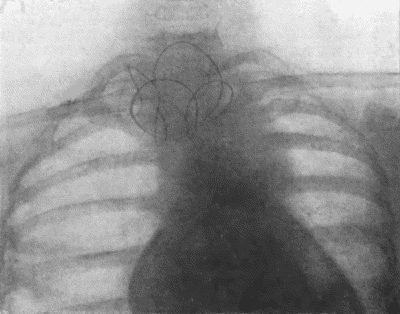

73.Radiogram of Innominate Aneurysm after Treatment by Moore-Corradi method 309

CHAPTER XII